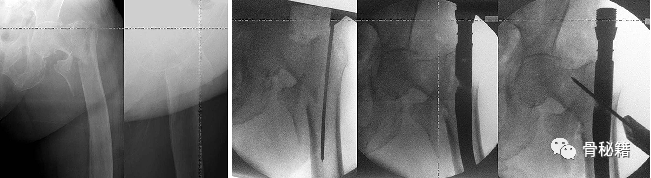

过于偏外的进针点导致髋内翻

进行调整后重新进钉